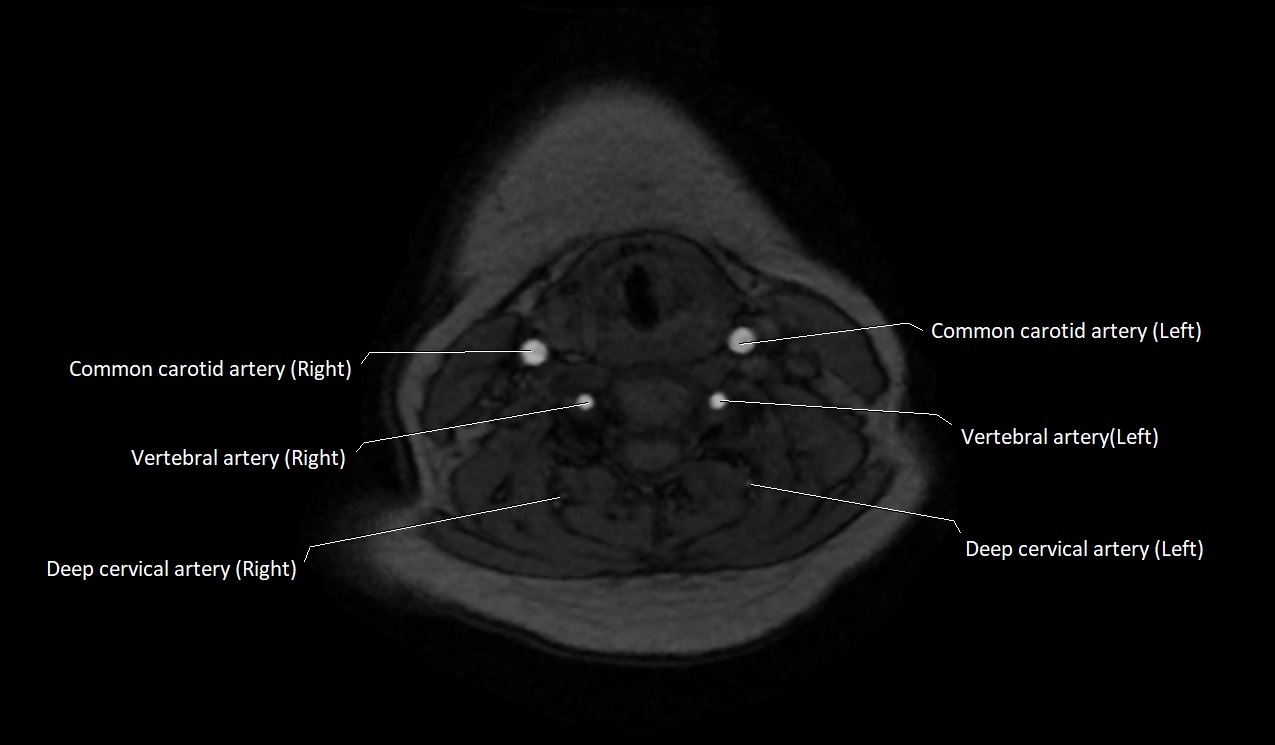

MRI images

image